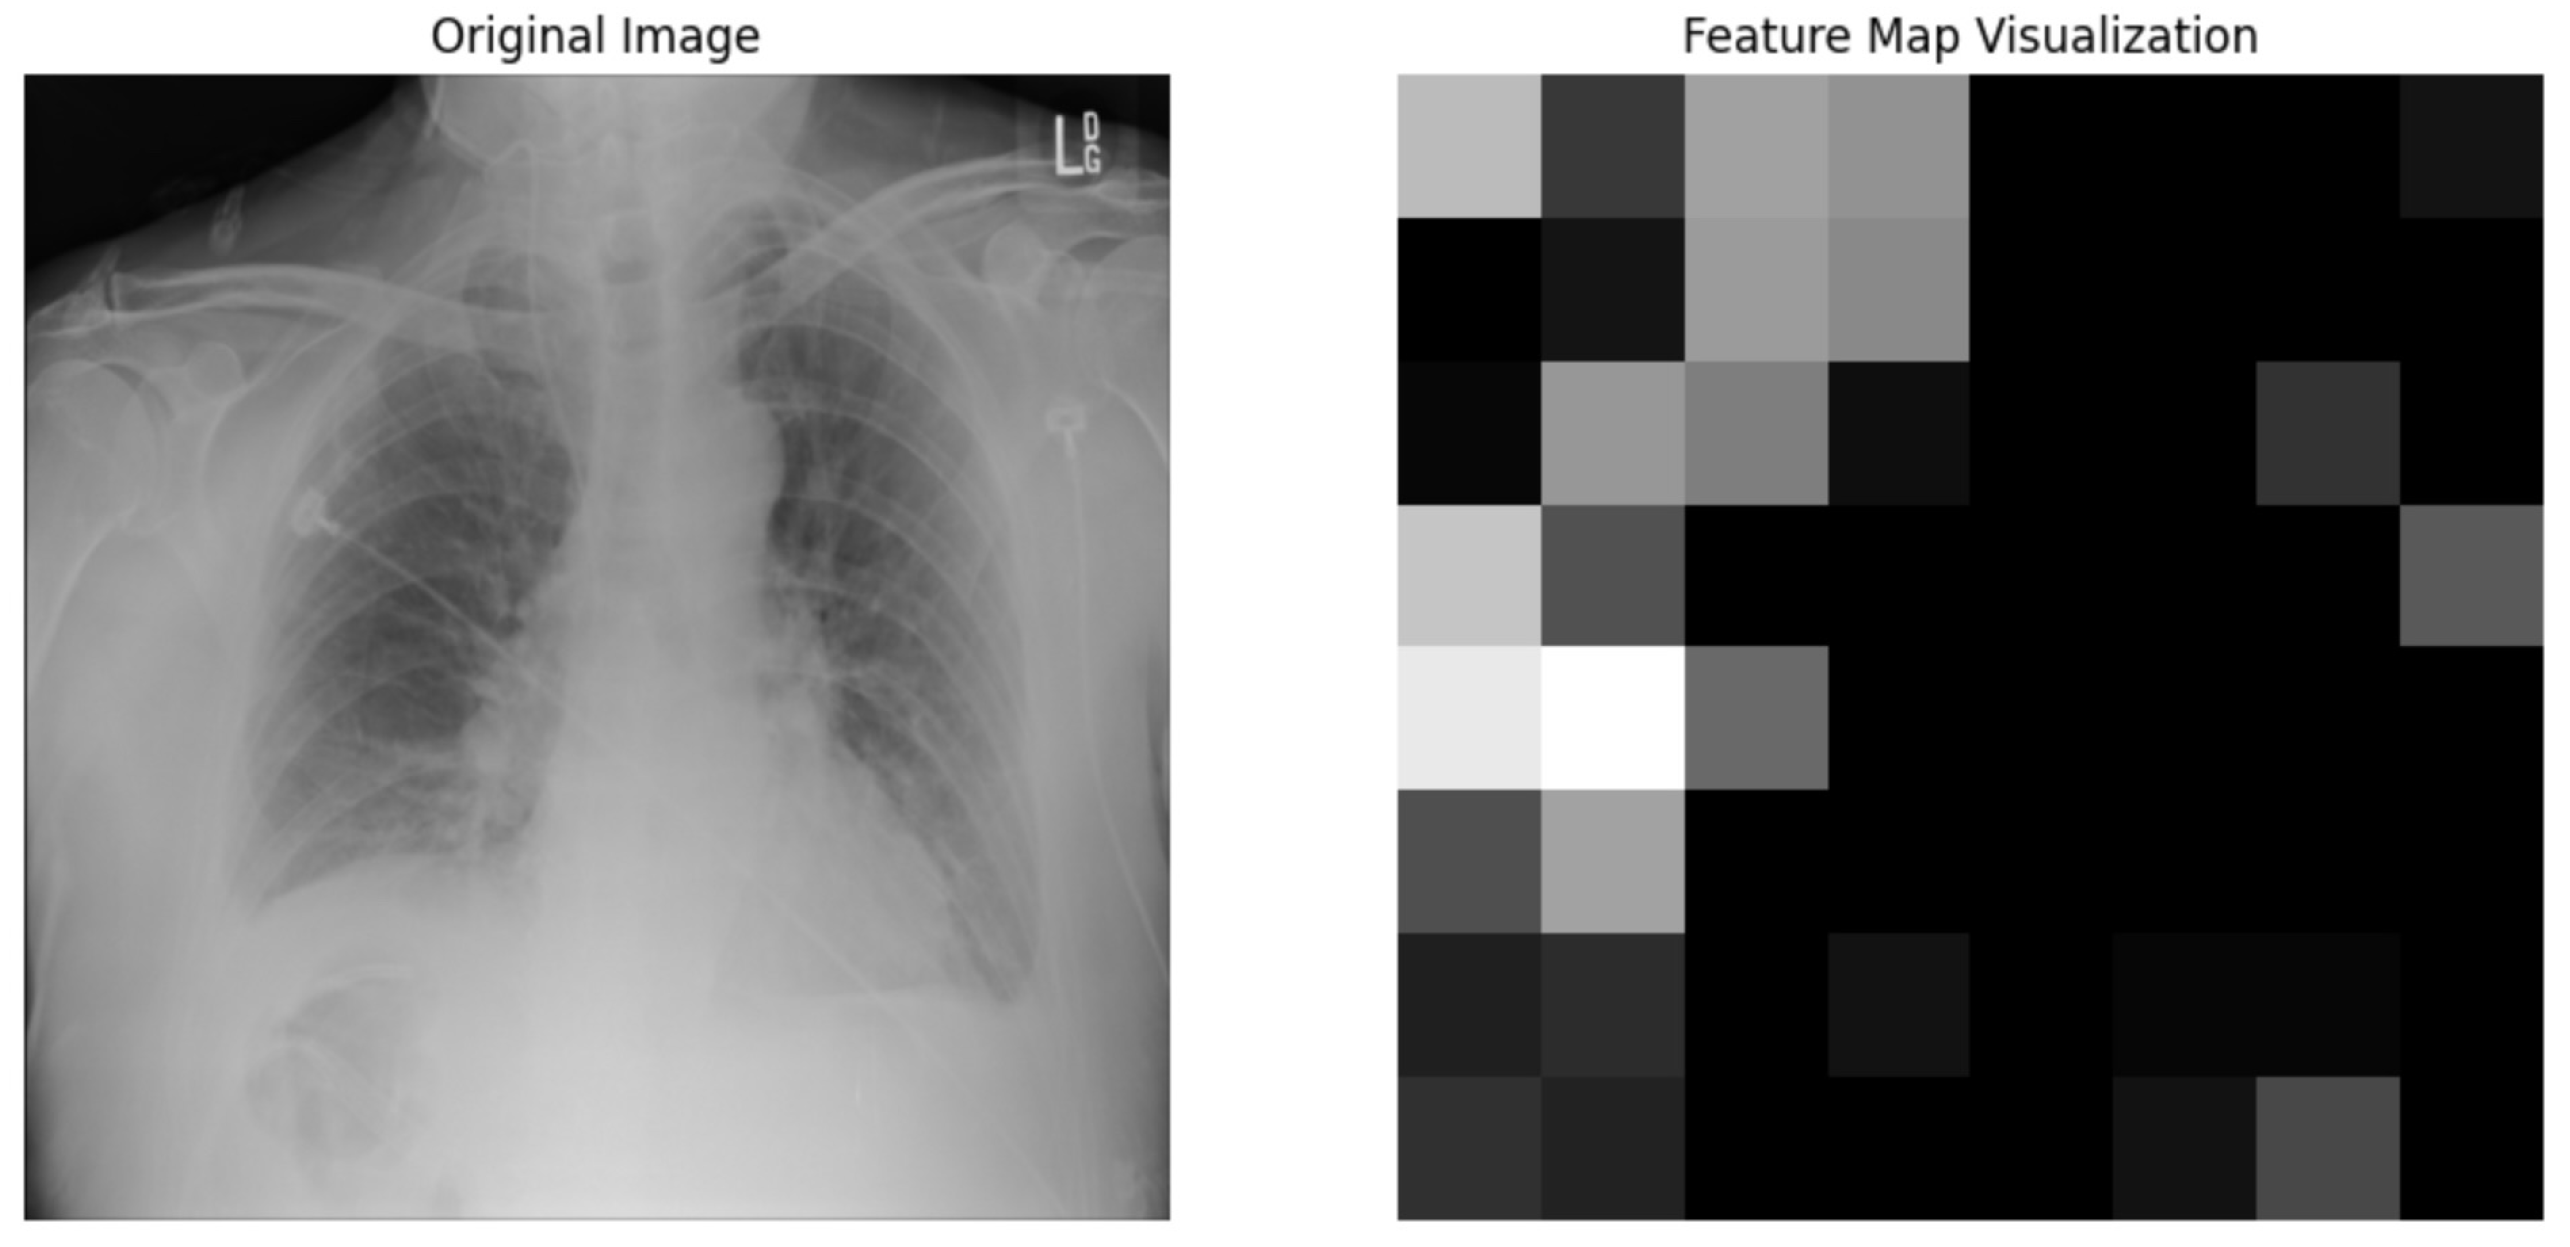

We used the ResNet50 algorithm for feature extraction and compared to other architectures like DenseNet121. Figure 12 ResNet50 employs residual learning with deep residual networks, effectively mitigating the precision of feature maps, which are critical for accurate segmentation and diagnosis in clinical settings. On the other hand, while DenseNet121 is lauded for its feature reuse capabilities and potentially lower model complexity due to fewer parameters, ResNet50’s streamlined data flow and gradient propagation provided a more robust framework for capturing and emphasizing relevant features in chest X-rays. It is crucial for detecting and diagnosing diverse and minute pathological changes within the lungs, offering profound insights into pulmonary conditions in medical imaging. Chest X-ray potential area mark in Figure 13 followed binary thresholding techniques in processing a chest X-ray image to isolate potential lung areas from the surrounding anatomical structures. Binary thresholding is a form of image segmentation that involves converting a grayscale image into a binary image, where each pixel is assigned a value of either 0 or 1 (black or white). The binary thresholding algorithm is particularly effective for enhancing lung tissue visibility against other body components by setting a pixel intensity threshold. Applying such a threshold highlights areas within the lungs that exceed a certain intensity level (shown in white), while less relevant areas remain black. This technique simplifies the image, allowing for clearer identification and analysis of lung regions that could contain pathological features. It aids in detecting anomalies like fluid build-up, masses, or unusual opacities that might indicate conditions such as pneumonia, tuberculosis, or lung cancer. ResNet architecture parameter in Table 8 and Table 9.